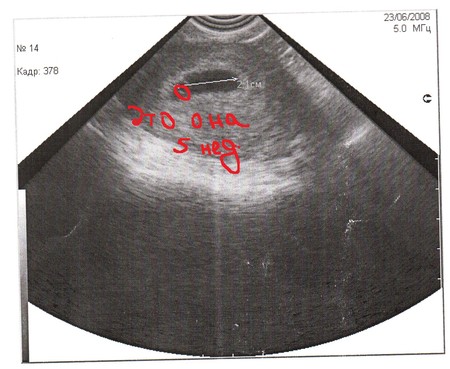

Вот это наши фоточки с УЗИ.

Тут нам 5 неделек